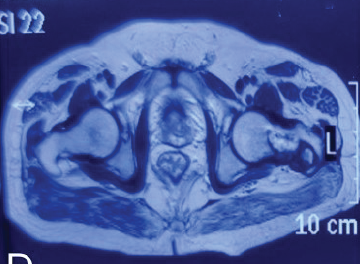

A Missed Case of Langerhans Cell Histiocytosis of the Proximal Femur after Total Hip Arthroplasty in an Adult: A Case Report

Sandeep Sehrawat , Mukund Madhav Ojha , Shivanand Gamanagatti , Vijay Kumar

………………………………p.57-61